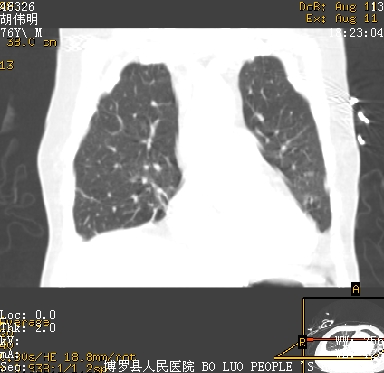

icu病人,几天都没明确诊断。m,76y,咳嗽、咳痰1周,伴气促,右胸痛入院,pe:t38.3c p135 r25 bp135/85。双肺可闻及大量湿罗音,心、腹未见明显异常。诊断:1心衰?2肺部感染?3冠心病?

11号ct

双肺感染性病变,下叶膨胀不全,胸水,左室大。

1)两肺感染性病变(右肺下叶肺脓肿可能)。2)双侧胸腔积液,以右侧为甚。

考虑双肺感染、右肺下叶肺脓肿伴双侧胸腔积液。

ards,肺感染性病变,右下叶实变,双侧胸腔积液,右侧为著,叶间胸膜积液,右上肺陈旧性tb纤维灶,左室大。